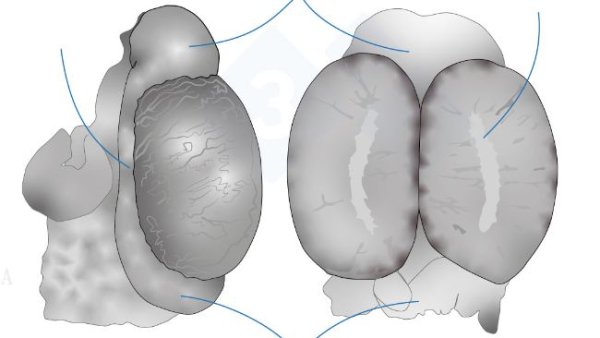

In diesem zweiten Teil behandeln wir das Herauslösen von Zunge, Luftröhre, Lunge und Herz in einem Stück. Wir entnehmen die Organe der Bauchhöhle, sowohl den Verdauungs- als auch den Harn- und Genitaltrakt. Im Kopf legen wir die Nasenmuscheln, das Großhirn und das Kleinhirn frei.